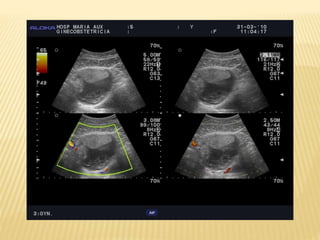

OVARIO

OVARIOS

 ESTRUCTURA ELIPSOIDEA

 EJE MAYOR VERTICAL GENERALMENTE

MEDIDAS:

D.L. 25-40mm.

D.AP. 10-15mm.

D.T. 12-20mm.

 Volumen normal:

MEF 9,8cm3

P.Menop.5,8cm3

Prepuber 3 cm3